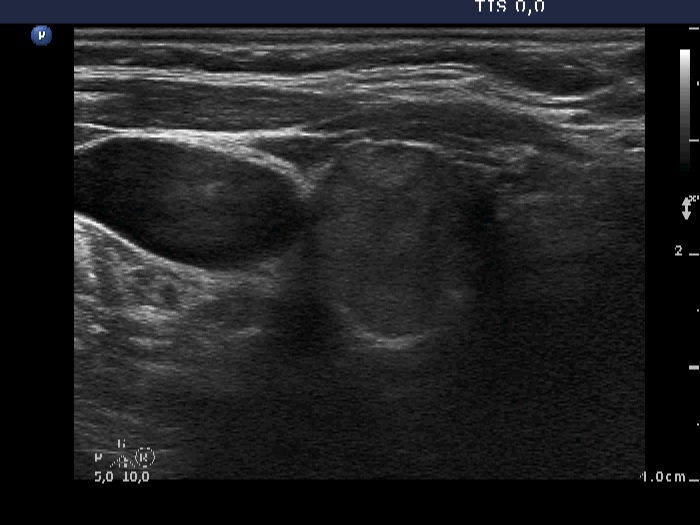

Discrete lesion or nodule in Hashimoto's thyroiditis - case 17 (782) (ultrasonographic picture 2)

Lower part of the right lobe, transverse scan. There is a moderately hypoechogenic part of the mass.